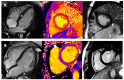

Cardiomyopathies are a heterogeneous group of myocardial diseases representing the first cause of heart transplantation in children. Diagnosing and classifying the different phenotypes can be challenging, particularly in this age group, where cardiomyopathies are often overlooked until the onset of severe symptoms. Cardiovascular imaging is crucial in the diagnostic pathway, from screening to classification and follow-up assessment. Several imaging modalities have been proven to be helpful in this field, with echocardiography undoubtedly representing the first imaging approach due to its low cost, lack of radiation, and wide availability. However, particularly in this clinical context, echocardiography may not be able to differentiate from cardiomyopathies with similar phenotypes and is often complemented with cardiovascular magnetic resonance. The latter allows a radiation-free differentiation between different phenotypes with unique myocardial tissue characterization, thus identifying the presence and extent of myocardial fibrosis. Nuclear imaging and computed tomography have a complementary role, although they are less used in daily clinical practice due to the concern related to the use of radiation in pediatric patients. However, these modalities may have some advantages in evaluating children with cardiomyopathies. This paper aims to review the strengths and limitations of each imaging modality in evaluating pediatric patients with suspected or known cardiomyopathies.